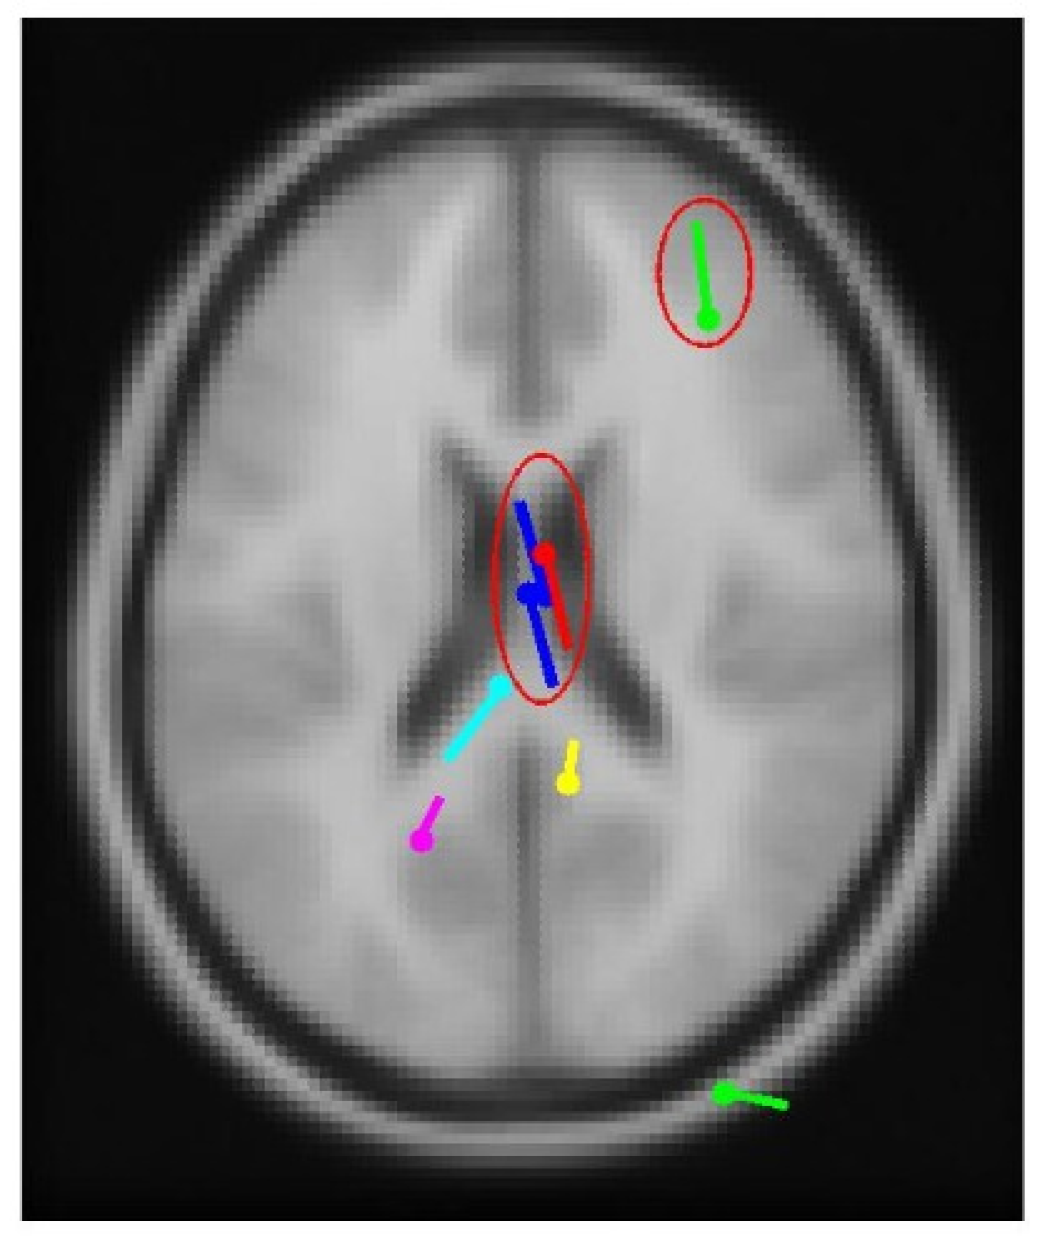

3.3. Real-World Patient Data